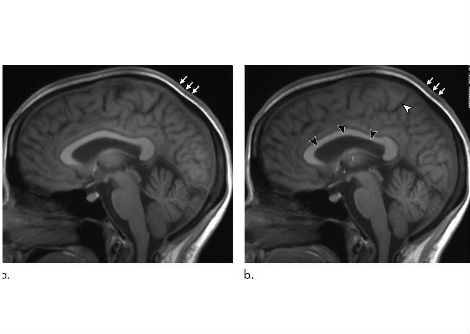

درس الباحثون نوعين من الخلايا العصبية في دماغ الفأر:

• خلايا AgRP العصبية الموجودة في النواة المقوسة تحت المهاد (hypothalamus)، وهي المسؤولة عن تحفيز الإحساس بالجوع.

• خلايا PVH العصبية الموجودة في النواة المجاورة للبطين تحت المهاد، وهي تساعد في كبح الجوع.

تتفاعل هاتان المجموعتان من الخلايا العصبية بشكل وثيق. ففي الظروف الطبيعية، ترسل خلايا AgRP إشارات مثبطة إلى خلايا PVH، ما يؤدي إلى الإحساس بالجوع. وعندما تُثبَّط خلايا AgRP، تصبح خلايا PVH أكثر نشاطًا، مما يقلل الشهية.

وجد الفريق البحثي أن لاك-في يعمل مباشرة على خلايا AgRP ويثبط نشاطها، مما يسمح لخلايا PVH بأن تصبح أكثر نشاطًا، وبالتالي يقل تناول الفئران للطعام. والأهم أن سلوك الفئران العام لم يتأثر، مما يشير إلى أن لاك-في يقلل الشهية دون آثار جانبية سلبية.